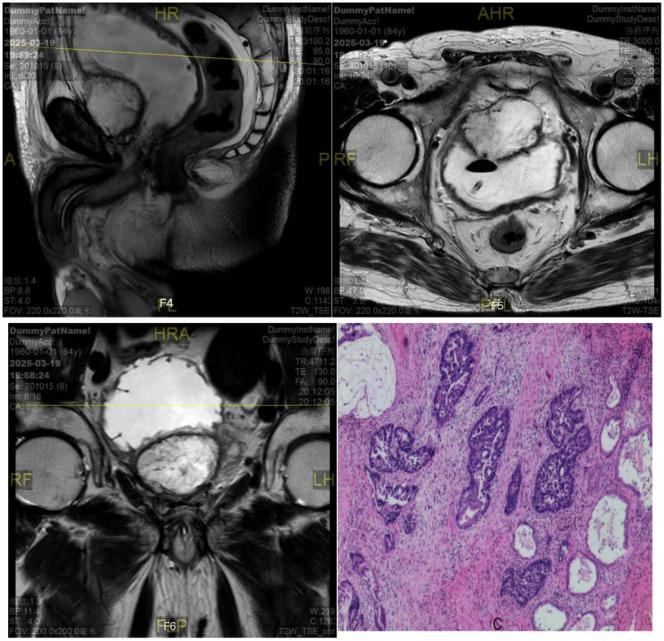

前列腺黏液腺癌伴极低前列腺特异性抗原水平及复发性疾病:一例报告

Mucinous adenocarcinoma of the prostate with extremely low prostate-specific antigen levels, recurrent disease: a case report.

Mucinous adenocarcinoma (MC) is a very rare type of prostate cancer, accounting for less than 1% of prostate adenocarcinomas, and its etiology is still unclear. Its clinical symptoms are similar to those of prostate hyperplasia and follicular carcinoma of the prostate, which are often misdiagnosed, and a definite diagnosis depends on pathological diagnosis, and the secretion of a large amount of mucus is its pathological characteristic. Surgery and endocrine therapy are the main treatment modalities, followed by radiation therapy and comprehensive therapy. Since this disease is rarely reported, in order to improve the understanding and diagnosis of clinically rare MC, we report a case of primary recurrent mucinous adenocarcinoma of the prostate and analyze its clinical features, pathological diagnosis, treatment and prognosis in the light of the literature.

摘要

黏液腺癌(MC)是一种非常罕见的前列腺癌类型,占前列腺腺癌的比例不到1%,其病因仍不清楚。其临床症状与前列腺增生和前列腺滤泡癌相似,常被误诊,明确诊断依赖于病理诊断,大量黏液分泌是其病理特征。手术和内分泌治疗是主要治疗方式,其次是放射治疗和综合治疗。由于该病报道较少,为提高对临床罕见的MC的认识和诊断,我们报告1例原发性复发性前列腺黏液腺癌病例,并结合文献分析其临床特征、病理诊断、治疗及预后。